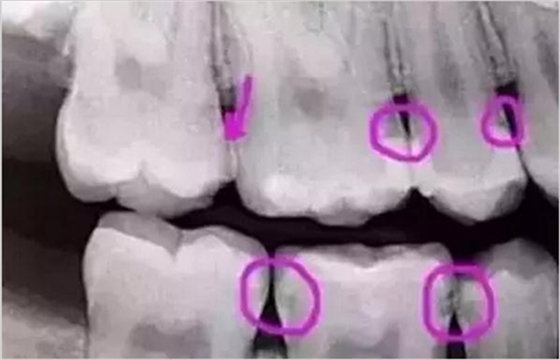

圈出來(lái)的地方或多或少都有點(diǎn)齲齒,但是有些你并不能看見(jiàn)。這些齲齒還淺不會(huì)讓你有什么感覺(jué),頂多吃東西塞牙,和冷水敏感而已。